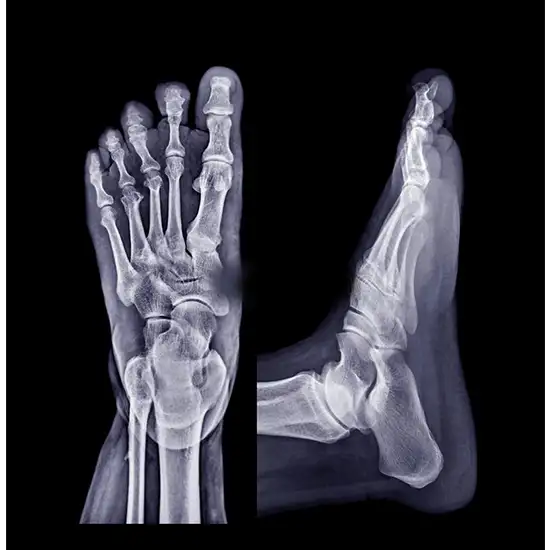

Right Foot X-ray AP LAT View

Right foot X-ray AP Lat view is a safe and easy way to get a picture of your foot from the front and side. An X-ray uses tiny amounts of radiation to take a picture of your foot, including its bones (like the bones in your ankle, the front of your foot, and your toes) and its soft tissues (like skin and muscle).